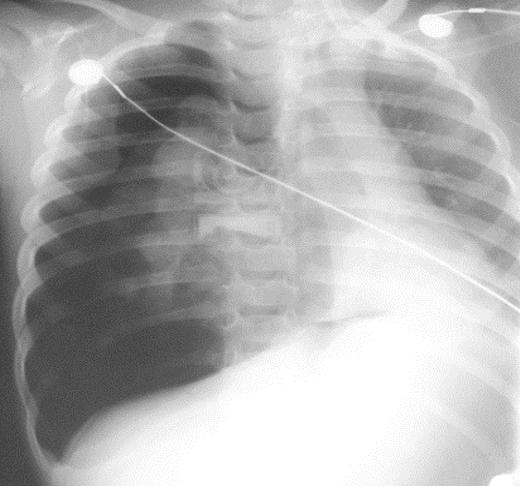

Figura 8.

(A) Una radiografía de tórax muestra una clavícula derecha rota con un gran neumotórax derecho y neumomediastino en una mujer de 24 años atropellada por un automóvil. (B) Una radiografía obtenida después de la colocación de un tubo torácico muestra un neumotórax persistente. Se observó una gran fuga de aire del tubo. La broncoscopia reveló una rotura completa del bronquio principal derecho